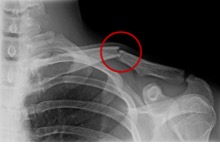

Omdat het sleutelbeen door zijn ligging zo makkelijk is te onderzoeken, kan de arts na zijn onderzoek meestal met zekerheid vaststellen of uw sleutelbeen gebroken is. Vaak zal de arts er voor kiezen aanvullend een röntgenfoto te maken.

Slechts in bepaalde gevallen is er een reden voor een operatie. Een harde reden voor een operatie kan zijn dat een botstuk door de huid dreigt heen te gaan. Ook kan een sterk afwijkende stand een reden zijn voor een operatie. De nadelen van een operatie (ontsierend litteken, infectiekans, uitbreken van fixatiemateriaal) wegen echter vaak niet op tegen de voordelen (standscorrectie). Uw behandelend arts zal samen met u een afweging kunnen maken hoe dat in uw specifieke situatie is. Bij sleutelbeen breuken waarbij de breuk helemaal aan de zijkant ligt, zal er wel sneller naar een operatieve behandeling worden geneigd. Indien er voor een operatie wordt gekozen, zal er meestal gebruik worden gemaakt van een plaatje met schroeven.